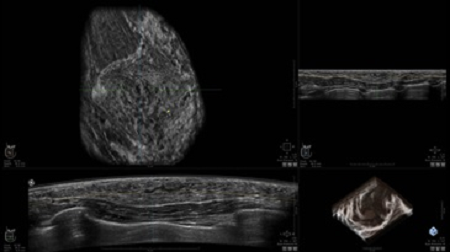

GE INVENIA ABUS – это современный УЗИ аппарат, который создан для точной и эффективной диагностики сканирования с высокой плотностью молочных желез. Выявляемость патологий раковых и предраковых стадий заболевания составляет 55%, что в конечном счете позволяет ставить врачу точные и своевременные диагнозы. Традиционные методы использования маммографии не показывают такой выявляемости, ограничиваясь лишь 3-38%.

УЗИ-аппарат GE INVENIA ABUS позволяет проводить максимально операторонезависимые процедуры, что значительно снижает риск неправильной постановки диагноза и сопутствующие издержки на обработку информации. Система готовит отчет в течение 3-х минут после сканирования, это безусловное преимущество по сравнению с обычным УЗИ сканером.

• Получение объемных 3D изображений с возможностью покадрового просмотра

• Получение изображений в поперечной плоскости (в реальном времени) и в коронарной плоскости (статическая, для указания нахождения соска)

• Отображение объемных 3D ультразвуковых изображений, которые состоят из традиционных поперечных и воссозданных коронарных и сагиттальных проекций

• Стандартизованная ориентация изображения: «толстый срез» в коронарной плоскости; поперечная; сагиттальная плоскость; радиальный и антирадиальный поворот изображения; просмотр исключительно области интереса